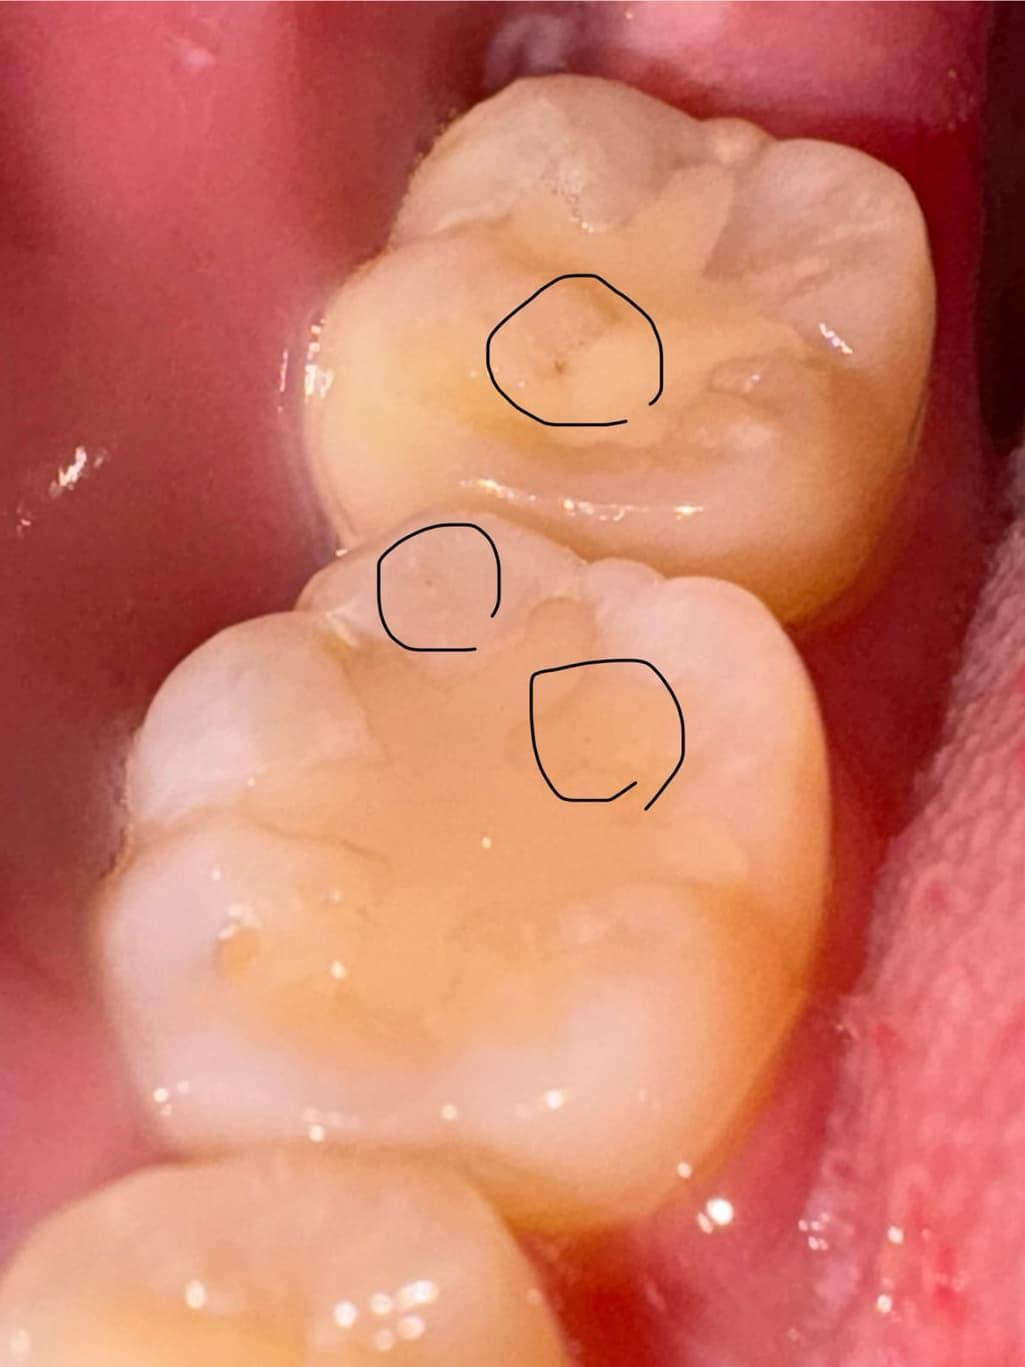

사진 내 표시한 부분이 충치인걸까요?

진료보기 전에도 사진처럼 검정부분이 존재했는데 선생님은 보시고도 충치가 없다고 하셔서 그냥 그런가보다 했는데 아파서 해당부분을 찍어서 사진으로 보니까 검정부분이 너무 잘 보여요

혹시 충치일까요? 아니면 홈이 파진부분이 빛의 각도 때문에 어둡게 보이는 걸까요?

사진으로 보이는 부분에는 충치가 있는 것으로 보이진 않습니다. 이전에 충전해놨던 재료의 구멍이 뚫린 것으로 보입니다. 크게 문제가 되진 않지만 걱정이 된다면 해당 부위를 치과용 재료로 충전할 수 있습니다.

사진에 보이는건 충치는 아니고 예전에 치료를 한곳이 틈이 생기면서 착색이 발생한거 같습니다.

엑스레이 찍어보는 것이 좋을 것 같습니다 하방 충치는 눈으로 안보일 수도 있고요 지금 사진상으론 변색일 수도 있고, 이차충치일 수도 있어보입니다